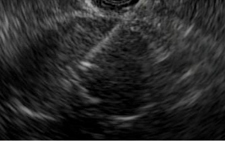

EUS-guided pseudocyst drainage

In other cases, such as to help diagnose pancreatic cancer, EUS is used to place stents (slender tubes) into the pancreatic duct or from the duodenum of the small intestine into the bile duct for drainage. In the case of individuals at high risk for cancer, EUS can help screen them for abnormalities and determine whether additional tests are needed. If a patient is diagnosed with pancreatic cancer, EUS can help determine whether the cancer is operable or not. If the cancer is not operable, EUS spares patients from unnecessary surgery.